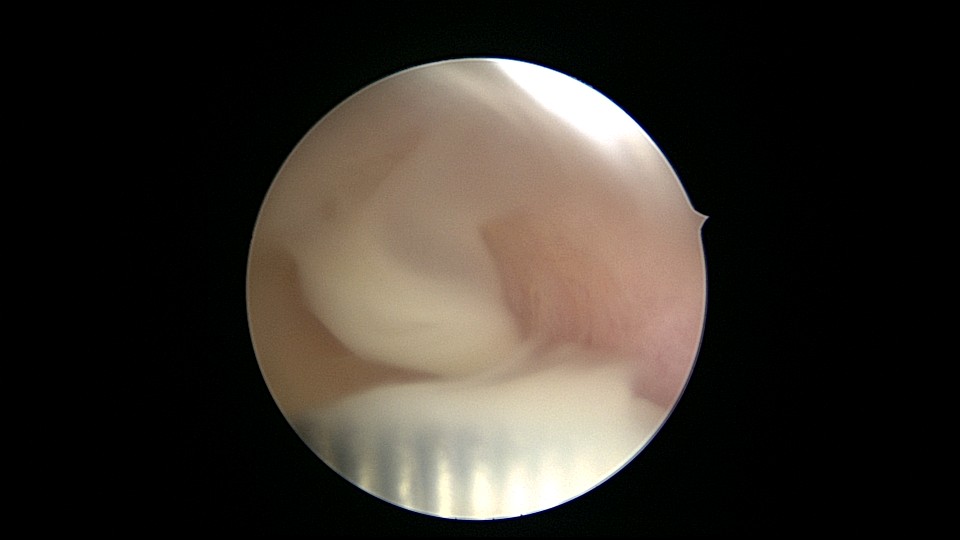

患者55岁,G5P1,顺产1次。安环20年,绝经8年。子宫后位,外阴、阴道及宫颈萎缩,宫深6.5cm,宫颈内口封闭粘连,镜鞘推开粘连,见灰白色脓液,O型环位置正常,异物钳顺利取出节育环,膨宫液冲洗脓液,宫腔无其他异常。